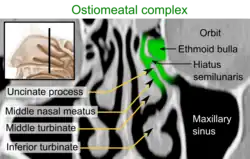

The lateral wall of each nasal cavity mainly consists of the maxilla. However, there is a deficiency that is compensated for by the perpendicular plate of the palatine bone, the medial pterygoid plate, the labyrinth of ethmoid and the inferior concha. The paranasal sinuses are connected to the nasal cavity through small orifices called ostia. Most of these ostia communicate with the nose through the lateral nasal wall, via a semi-lunar depression in it known as the semilunar hiatus. The hiatus is bound laterally by a projection known as the uncinate process. This region is called the ostiomeatal complex.[3]